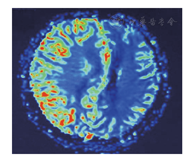

磁共振PWI特点:脑卒中样发作初期,病变区脑血流的储量下降,而自卒中发作后3 h开始到发病后的8个月左右病灶区域的脑血流增加。其原因可能由于病变急性期发作后乳酸堆积,而高乳酸血症导致血管舒张,病变区呈高灌注。灌注成像可见脑血流量明显增高。慢性期主要是能量供应不足导致细胞毒性水肿,出现皮质萎缩和多发性软化灶,病变周围出现胶质细胞增生和小血管增多[11],所以通常表现为脑血流量正常或减低。本组复发病例14例,脑内病灶新旧并存,急性病变区PWI呈高灌注,慢性病变区PWI呈低灌注。与文献报道一致。灌注成像对于MELAS诊断意义较大,尤其是急性期病变,由于乳酸造成病变区微小血管扩张,是病变区血容量及血流量明显增高,呈高灌注状态,而梗死及炎性病变因血流动力学改变病变区多呈低灌注状态。